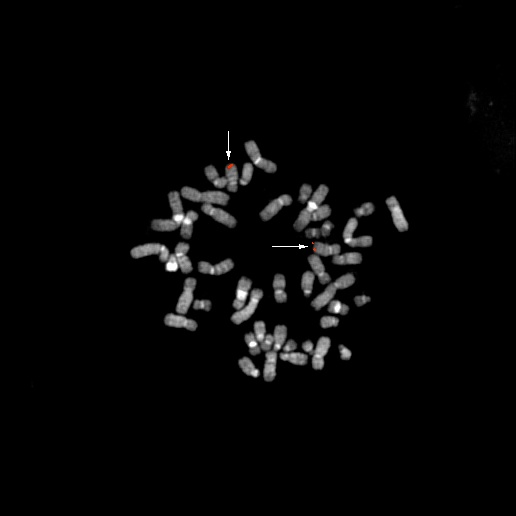

bA16P8